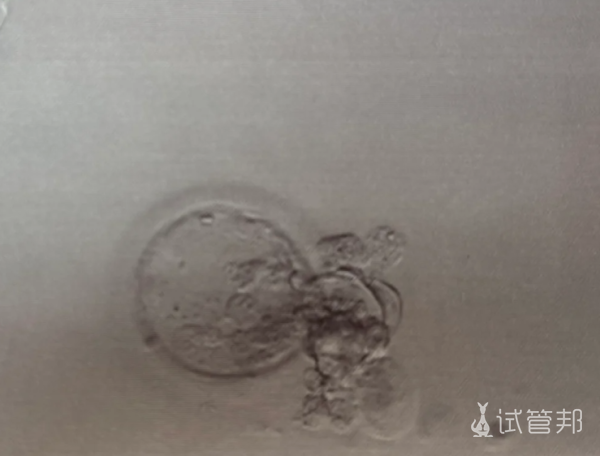

* 图片来源于网络,如有不当请联系删除